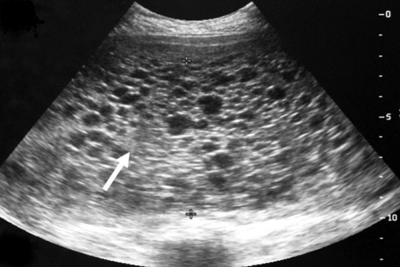

De diagnose mola-zwangerschap wordt gesteld op basis van het door de arts uitgevoerde lichamelijk onderzoek in combinatie met de bevindingen die worden gevonden bij het aanvullend onderzoek. Bij het aanvullend onderzoek wordt onder andere bloedonderzoek gedaan. Hierin worden zeer hoge concentraties van het zwangerschapshormoon HCG gevonden. Verder wordt er een echografie van de uterus gemaakt. De mola-zwangerschap is op het echografiebeeld te herkennen aan het karakteristieke druiventros- of honinggraatbeeld (zie onderstaande afbeelding). De combinatie van een hoge concentratie HCG in het bloed en het karakteristieke echobeeld pleiten sterk voor de diagnose mola-zwangerschap. De definitieve diagnose wordt echter gesteld door weefselonderzoek uit te voeren op het embryonale weefsel, maar dit kan vaak pas nadat de mola-zwangerschap verwijderd is.